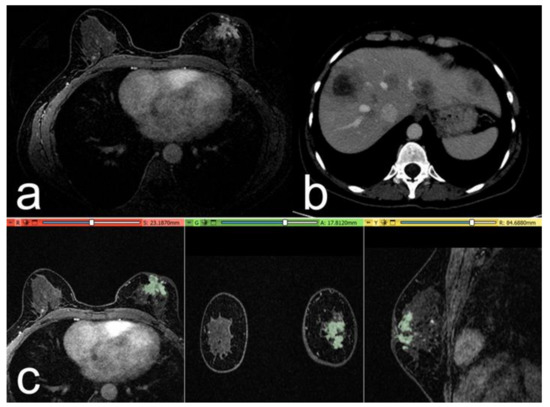

Figure 3.

Case of a 52-year-old woman with a G3 triple negative invasive ductal carcinoma, Ki-67 of 30%. (a) The post-contrast image shows a retroareolar irregular non-mass-enhancing lesion in the left breast. (b) At 1-year follow-up: post-contrast axial CT image, with some metastatic nodules in the liver parenchyma. (c) Representation of the extraction of the segmentation mask.